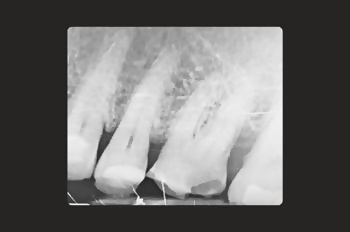

Root canal treatment is needed when the tissues inside a tooth become damaged, infected, or inflamed due to deep decay, cracks, injury or repeated dental procedures on the same tooth.

Common symptoms of a dental infection include persistent pain, sensitivity to cold and cold that lingers, swollen or tender gums, a pimple-like bump on the gum next to a tooth (a sign of an abscess), or tooth darkening and discolouration.

An infected root canal can cause intense pain, abscess formation, tooth loss, and even the infection spreading to other parts of the body if left untreated.